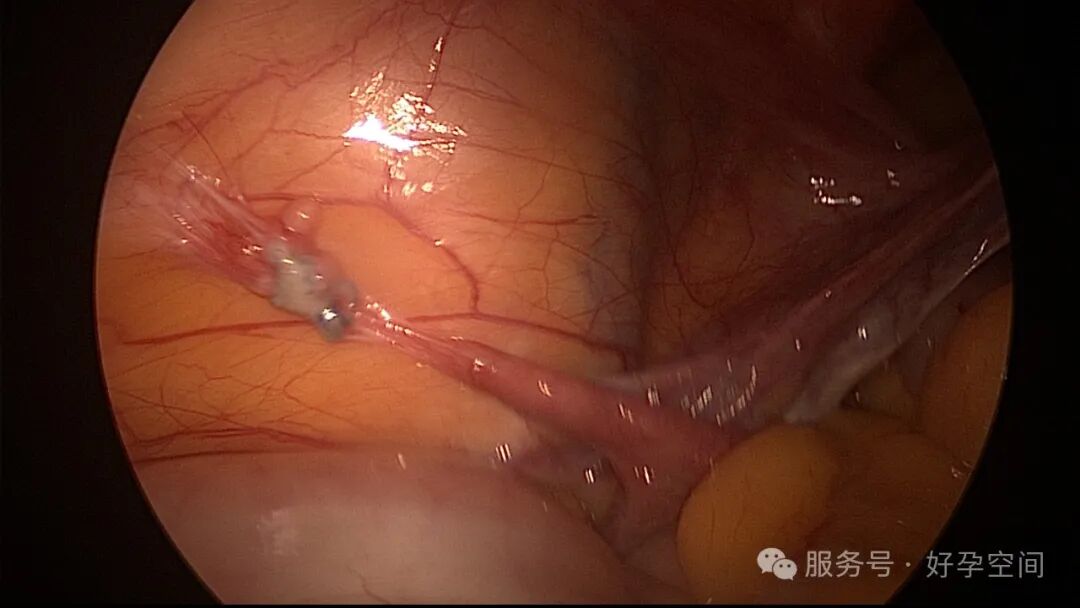

试管前宫腔镜检查